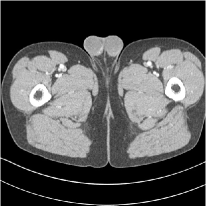

III.C.3. Analysis of Residual Maps

Here, we investigate the residual images over the layers of the MARS7 model. Fig. 12 displays the image reconstructed with MARS7 along with the residual images in different layers. The residual images are generated by applying the restoring operation to the corresponding columns of each residual matrix , forming images . Essentially, all the columns of are transformed into patches and accumulated back in the image to form the residual image in the th layer. We can observe that the residual images in the first three layers contain explicit structural information and we still find some delicate details in the fourth and fifth layers. However, we hardly see any valuable features in the residual images for the following layers, which is consistent with the fact that the transform is overwhelmed by noise in quite deep layers. Therefore, the ceiling for the potential of multi-layer sparsifying transform model may be 5 or 7 layers. The quantitive result also implies the same conclusion.